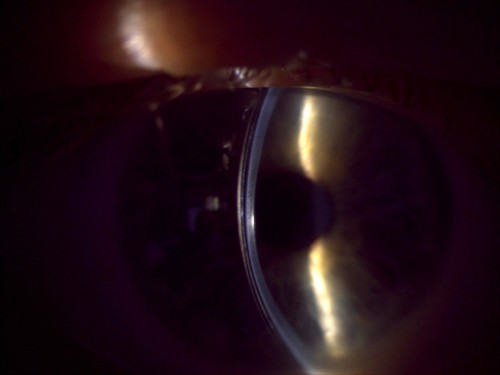

A 53-year-old male patient presented to our clinic for a specialty contact lens evaluation after being referred by his cornea specialist for an updated fit. The patient has an ocular history of keratoconus in both eyes, dry eye disease, and asthma. He had a history of RGP contact lens use for 25 years. The patient had issues with dry eye spells that caused the contact lens to pop out of his eye, and sports activities often caused dislodgement of the lens. He used over-the-counter reading glasses +1.75 for all near work and described overall disappointment in his reading vision.

Upon conversing with the patient, we learned that he was seeking a lens option that provided similar optical quality to GPs with better stability, and he did not want to use reading glasses. After completing tomography scans and refraction, we determined that a scleral lens was the best option. The manifest refraction measured at -2.25 -5.25 @ 084 and 0.00 -1.75 @ 090 with a visual acuity of 20/40 OD and 20/30 OS with glare.

A scleral lens was applied to both eyes as a trial, and the patient noted immediate improvement in comfort and stability. Mild posterior tear film debris was caused by inferior lens decentration in both eyes. With the quadrant-specific haptics in the lens design, minor changes were instilled to improve comfort and fogging issues. We then completed an over-refraction and demonstrated a +1.50 for reading power, and the patient read J1.